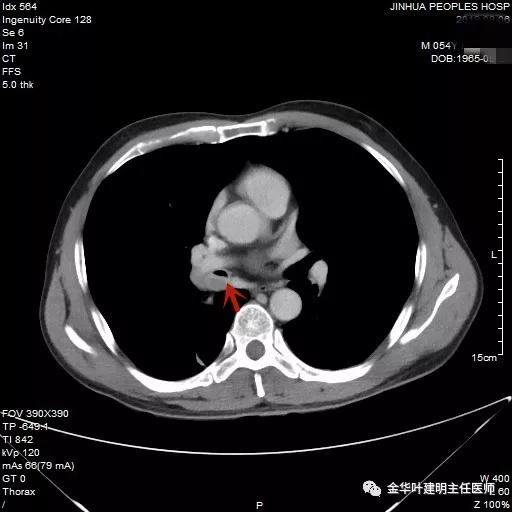

可见右中间支气管开口处新生物,堵塞管腔,明显是肿瘤,但因当时服用波立维与阿斯匹林双抗治疗,停的时间还不够,所以没有活检,而刷检没找到癌细胞。请我会诊时,我看了李某的胸部CT增强:

上图示上叶支气管通畅

上图示中间支气管起始处似乎还算正常

上图示中间支气管起始处以下3毫米处已经管壁增厚异常

上图示肿瘤堵塞管腔

上面各图示肿瘤位于肺门部,堵塞下叶及中间支气管

我们仔细看了增强CT,纵隔未见确切疑似转移的肿大淋巴结,这样的情况下,是不是再次气管镜活检,还是直接可以手术?当然从原则上来讲,应该再重新纤支镜检查,再活检以取得病理确诊后,再行手术。但个人以为,从影像及气管镜所见来讲,临床诊断已经可以确定为肺癌,而且中央型的以鳞癌为多见,当然也有的会是小细胞癌,不过小细胞癌一般很早就会有纵隔淋巴结转移,如果患者及家属理解,我认为从减少痛苦、节约经费、节省时间等方面考虑,直接手术也基本不会错的。当然所有的利弊与可能都要如实与患者及家属沟通,并征求他们的意见,最终李某及家属选择不再重新纤支镜检查与活检,要求直接手术。